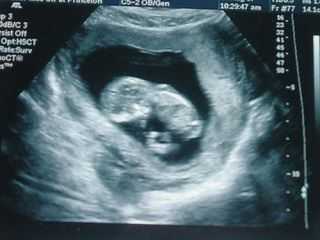

Многие будущие матери интересуются, как выглядит плод. На этом сроке беременности УЗИ позволяет увидеть следующие внешние признаки:

На 12 неделе беременности размер плода составляет приблизительно 7-10 см, а вес — 15-20 г. Примечательной особенностью является то, что плод на 12 неделе беременности все меньше похож на эмбрион. Но при этом ребенок имеет пока еще большую голову, хотя все больше напоминает крохотного человека.

УЗИ на 12 неделе беременности является запланированным. Оно позволяет оценить размеры плода и правильность его развития. Одновременно с этим впервые фиксируется предположительный срок родов. Необходимость УЗИ при беременности в 12 недель объясняется тем, что на этом сроке нужно определить:

Часто женщины хотят на УЗИ увидеть пол ребенка. Это возможно только при использовании высокочувствительной аппаратуры. Но при наличии современного оборудования иногда можно будет увидеть только то, как выглядит плод на 12 неделе.

Это объясняется тем, что в этот срок для малыша в матке достаточно места для того, чтобы он мог находиться в любом положении. Следовательно, далеко не всегда получается рассмотреть его половые признаки.

УЗИ на 12 неделе

На этом сроке врач-гинеколог направляет женщину на первое ультразвуковое исследование. В это время определяются размеры плода и ориентировочная дата родов. Будущая мама впервые видит своего малыша, маленького человечка, которого совсем скоро она прижмет к груди. Также первое УЗИ отслеживает более важные показатели.

Оцениваются размеры матки и ее тонус, состояние и расположение плаценты, уточняется наличие или отсутствие внематочной беременности, а также точное количество плодов в матке женщины. Во время исследования будущая мама впервые видит свое чадо. Он еще слишком мал, и без помощи доктора трудно понять, что именно изображено на экране. Поэтому задавайте вопросы без стеснения, можете попросить показать личико. Вы не «увидитесь» до следующего скрининга, поэтому ловите драгоценные мгновения, запоминайте, какой он крошечный.

На пальчиках ручек и ножек будущего ребенка появляются зачатки ногтей, а на коже – первый волосяной покров. Активно развиваются мышцы. УЗИ на 12 неделе беременности может показать, как плод переворачивается и кувыркается, отталкиваясь ножками от стенок матки, хотя эти движения еще непроизвольны. У малыша начинает развиваться костная система, работать кишечник (перистальтика). В крови появляются лейкоциты. К 12 неделе у малыша сформирована щитовидная железа, гормоны которой регулируют обмен веществ и отвечают за рост ребенка.